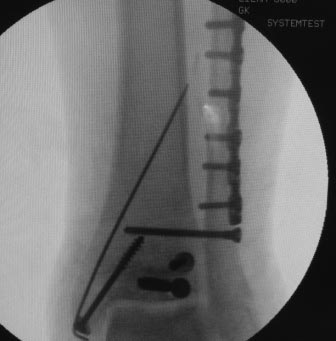

Уважаемые коллеги, всем огромное спасибо за рекомендации. Сегодня прооперировали. Презервативы в операционной оказались кстати :)

Фото синтеза прилагаю. Качество не ахти, так как фоткал с экрана. Но все видно.